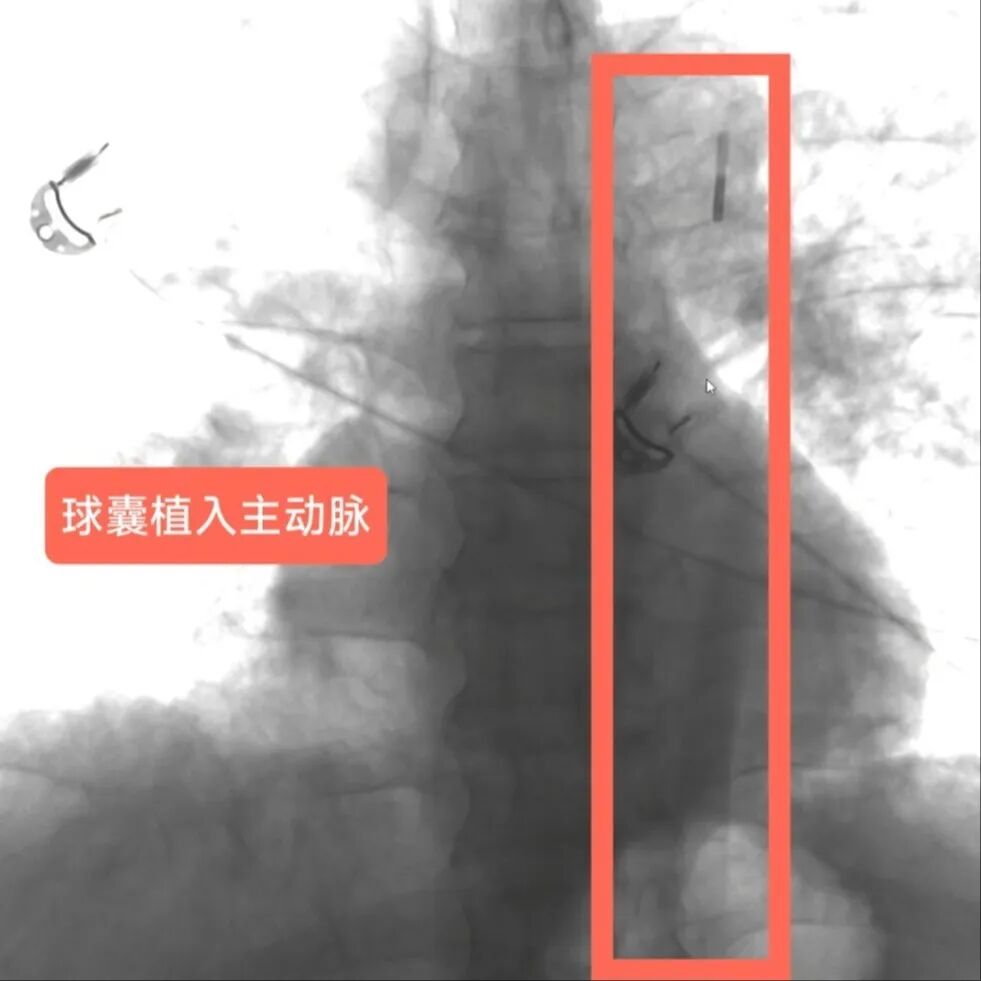

在疏通血管的过程中,钟先生还出现了血压下降、呼吸困难等危险情况。关键时刻,团队紧急启用IABP技术,李驹植入IABP球囊,改善冠状动脉血流,稳住患者血压,为营救患者争取时间,之后迅速植入支架,开通血管,稳定钟先生心脏血液循环。经过近3小时的紧张手术,钟先生的堵塞血管成功疏通,生命体征逐渐稳定,随后转入危急重症中心(ICU)进一步治疗。

IABP将球囊植入主动脉,植入后IABP显示球囊运行良好

李驹指导进行IABP调试